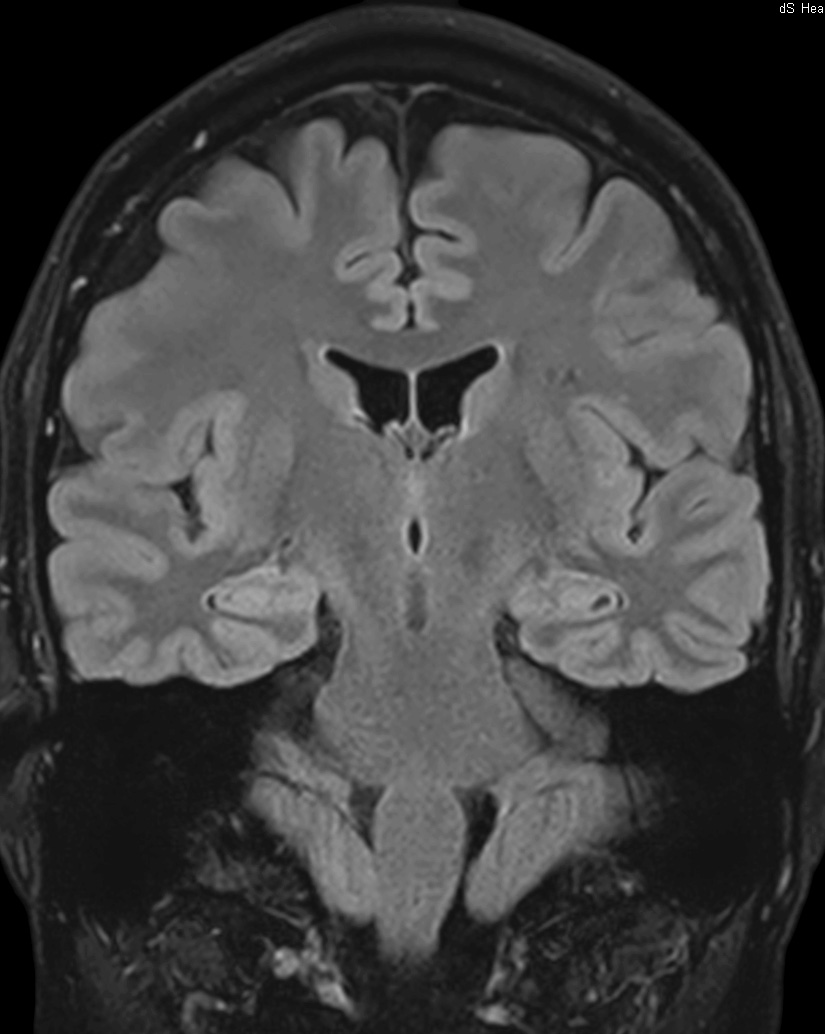

Hippocampus